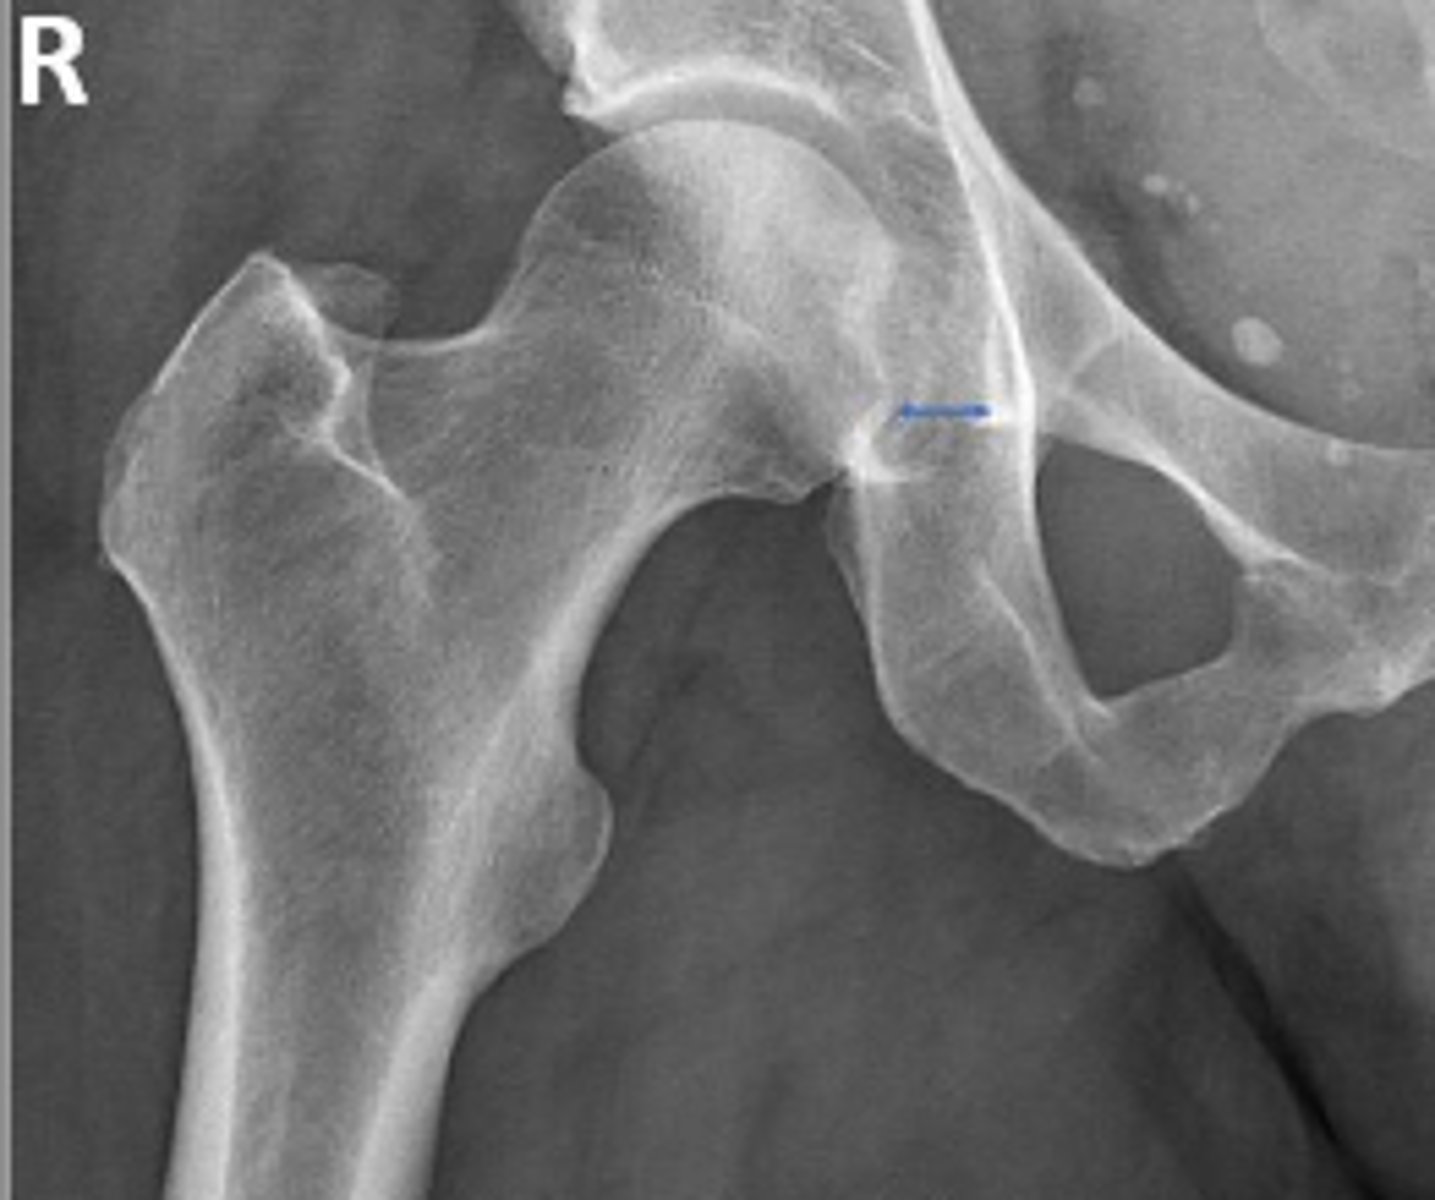

AP right hip

What is the radiographic view?

Teardrop distance

What is the name of the assessment?

6-11mm

What is the normal range for this assessment?

The distance between the most medial margin of

the femoral head and the adjacent pelvic

teardrop

What are the osseous landmarks for this assessment?

Yes (normal is 6-11mm)

Is the measurement within normal limits?

Femoroacetabular joint inflammation

Name 1 condition that may result in a measurement of 15mm?

AP pelvis and AP hip views

Name 2 radiographic views for this assessment?

Late stage degenerative joint disease

Protrusio acetabuli

Name 2 conditions that may result in a measurement of 3mm?

Waldenstrom's sign

What is the named sign if this assessment has a value > 2mm difference

between the left and right side?